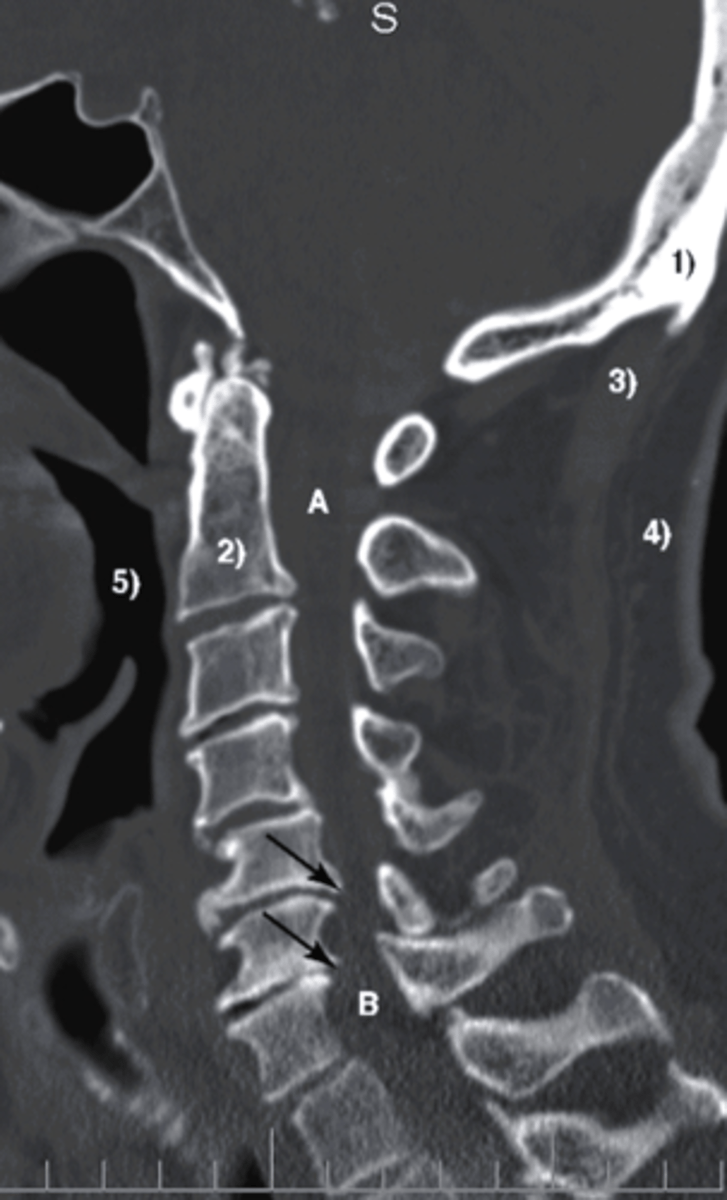

CT

what type of imaging study is this?

a.MRI

b. CT

c. Bone Scan

d. diagnostic ultrasound

displacement

What is identified by A in this image?

a. edema

b. displacement

c. bruising

d. osteophyte